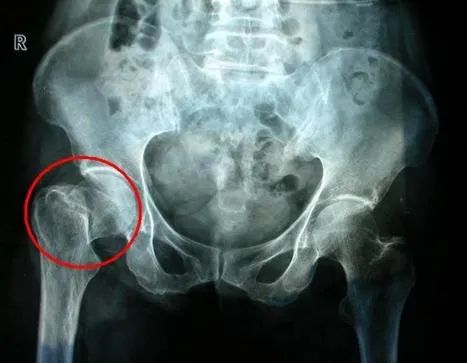

最为可怕的是,老年人在摔倒过程中一个特别容易骨折的部位就是髋部。

髋部属于下肢骨骼,髋部骨折会严重影响老人的行走功能。老人常见的髋部骨折有两种,一种是股骨颈骨折,另外一种是股骨粗隆间骨折。股骨颈部位血液供应不好,如果做内固定手术,远期很容易发生股骨头坏死。

股骨颈骨折